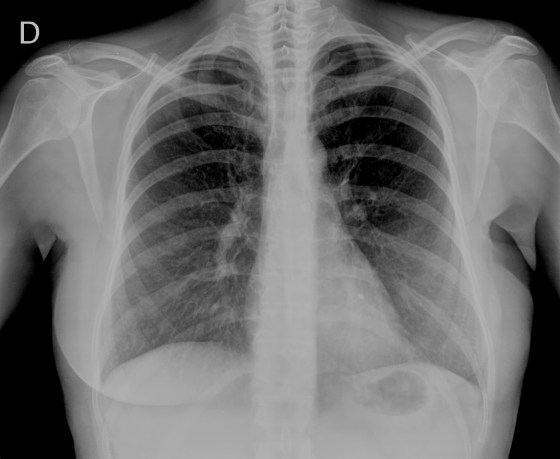

- Por la clínica presentada, debemos descartar un posible neumotórax. Sin embargo estamos ante una placa radiográfica con mala técnica.

- Se recomendó volver a realizar la radiografía, observar a continuación:

EXPOSICIÓN:

La penetración es la correcta cuando podemos visualizar la vértebras en su totalidad y las costillas a través del corazón.

El contraste es el adecuado si se pueden difrenciar adecuadamente estructuras con diferentes densidades: partes blandas, plumón y esqueleto.

La definición es buena si conseguimos que el paciente esté totlamente quieto durante la realización de la placa.